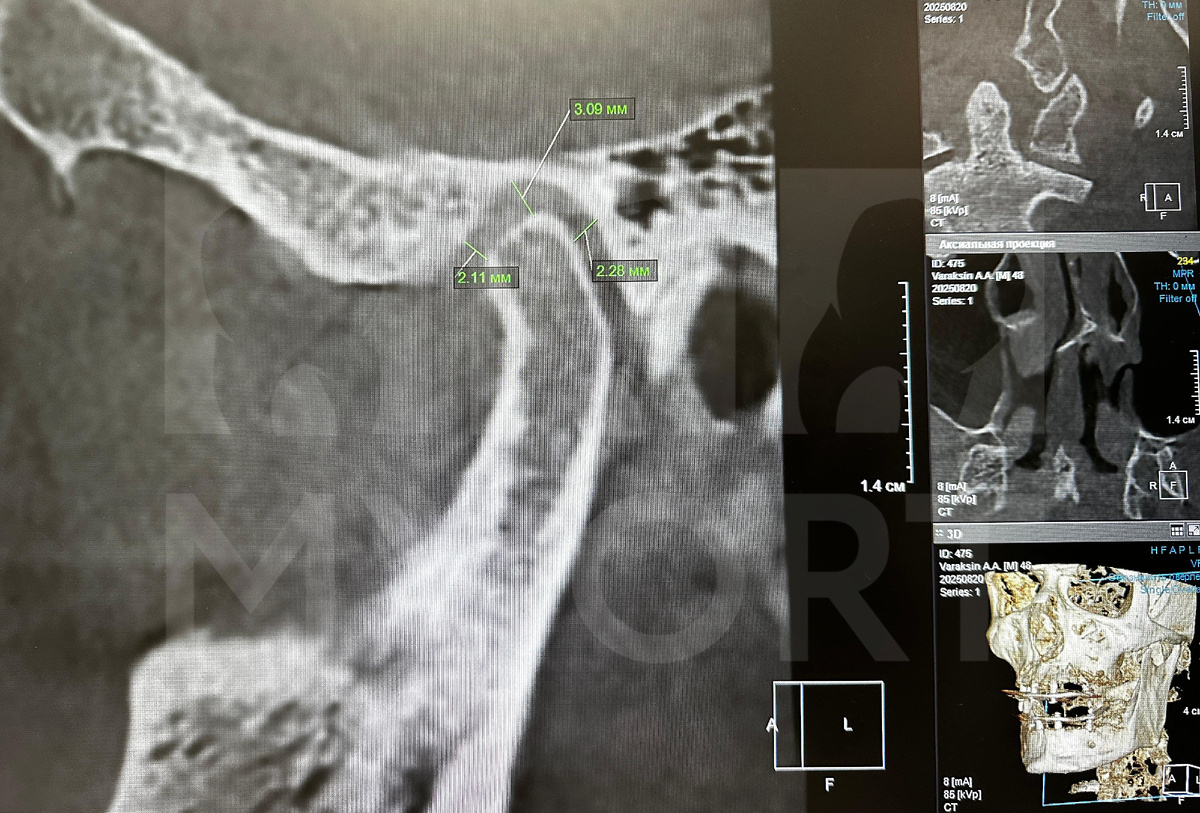

Пациент приехал ко мне из другого региона, не из Санкт-Петербурга. Поэтому первая консультация по результатам КЛКТ у нас проводилась онлайн.

Уже на первом этапе диагностики было видно, что собственные зубы пациента полностью несостоятельны, требовалась полная реабилитация.

На снимках у пациента был виден выраженный генерализованный пародонтоз. Он разрушил не только мягкие ткани, но и костную структуру вокруг зубов.

Визуализация КЛКТ